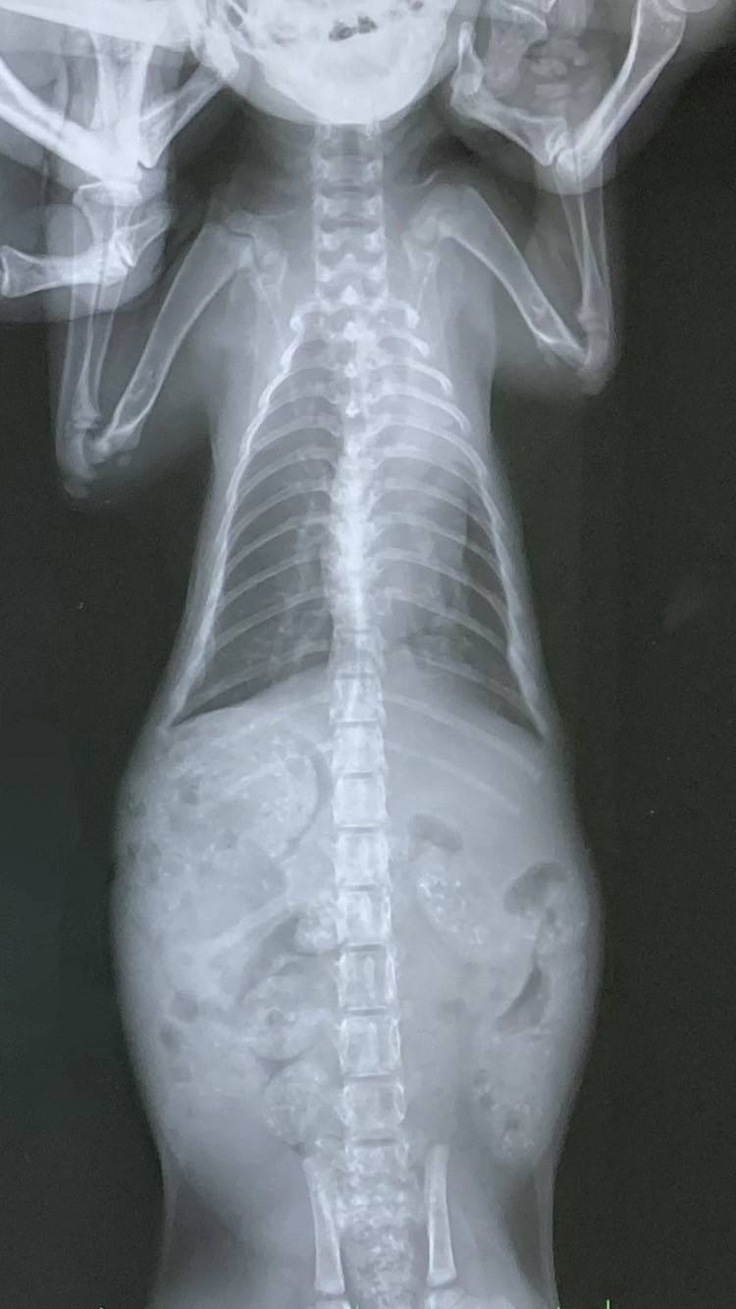

子猫ちゃんたちの通院日で診察とレントゲンを撮ってもらいました。体重が2匹とも900gで標準よりも少し大きいぐらいだと言われました。肺炎は分かりにくいけれど、少しずつ良くなっていると思う、ナイトの漏斗胸も良くなってきているから軽度のままでいけるのではないかと嬉しいお言葉をいただくことが出来ました。

まだ肺は完璧に綺麗になっているわけではないので、前回と同様の内服薬を1週間分もらってきました。完治することを願い、1日2回頑張って内服してもらいます。